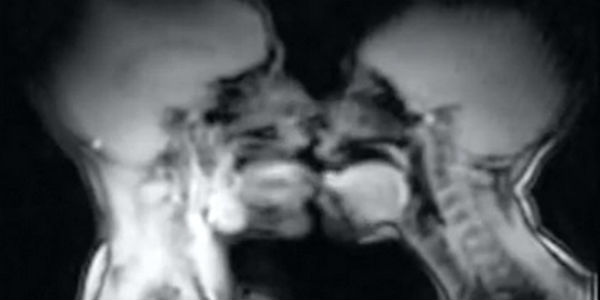

Sólo tal vez te hayas preguntado cómo se ven las relaciones sexuales dentro del cuerpo. Aquí está la respuesta: el canal Vox, de YouTube, compartió escenas del coito vistas con resonancia magnética. Pero además, el video muestra otras imágenes, como lo que sucede al hablar o al dar a luz. Los escáneres de resonancia magnética captan las imágenes en movimiento a partir de fuertes campos magnéticos que interactúan con los protones que habitan en nuestro cuerpo. A diferencia de los Rayos X, no usan radiación nociva.